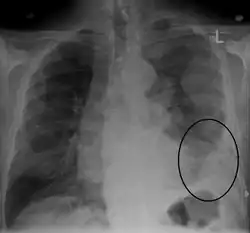

| CT scan showing a left sided mesothelioma with an enlarged mediastinal lymph node | |